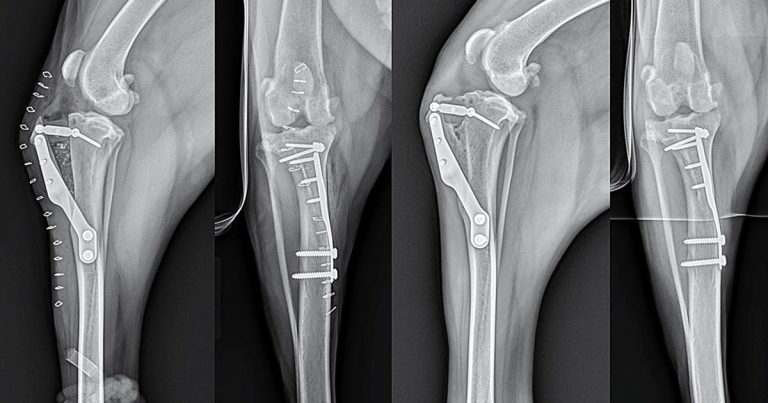

Figure 4. Mediolateral and caudocranial views taken immediately postoperatively (left) and eight weeks postoperatively (right) following routine tibial tuberosity advancement for stabilisation of a cranial cruciate deficient stifle in a five-year-old Labrador retriever.

An oscillating saw is used to free the tibial tuberosity via a frontal plane osteotomy. A metal cage is placed at the proximal aspect of the osteotomy to advance the tibial tuberosity and this is held in place using two screws. The cages are available in different widths, which allows the amount of advancement to be tailored to the patient based on preoperative templating to create the appropriate PTA. A plate that acts as a tension-band is placed from the tibial tuberosity to the tibial diaphysis to stabilise the tibial tuberosity in the new position. The plates are held in place using either screws or tines in the tibial tuberosity (depending on the manufacturer of the implant) and screws in the tibial diaphysis. A bone graft may be placed at the osteotomy site depending on the surgeon’s preference (Figure 4).

The most frequent complication observed was late meniscal tears, which are a known complication associated with the CrCL deficient stifle and are likely not dependent on the choice of method for surgical stabilisation, as previously discussed. Although, initially, the rate of late meniscal injury appeared to be higher following TTA than that reported following TPLO, later studies have not supported this finding. Radiographic healing is reported to occur between 8 to 10 weeks postoperatively for TTA (Figure 4).